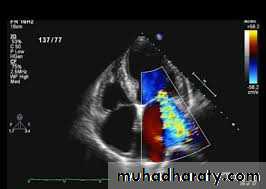

2D Echo cardiography –

valve edema ,mitral regurgitation, LA & LV dilatation, pericardial effusion, decreased contractility.

Echocardiography